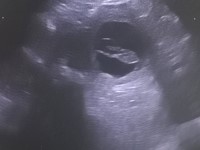

Heute beim Ultraschall gewesen. Valentina ist tragend. Wir haben mehrere Fruchtblasen erkennen können. Man kann auf dem Bild den Kleinen in der Blase erkennen

Wir freuen uns total.